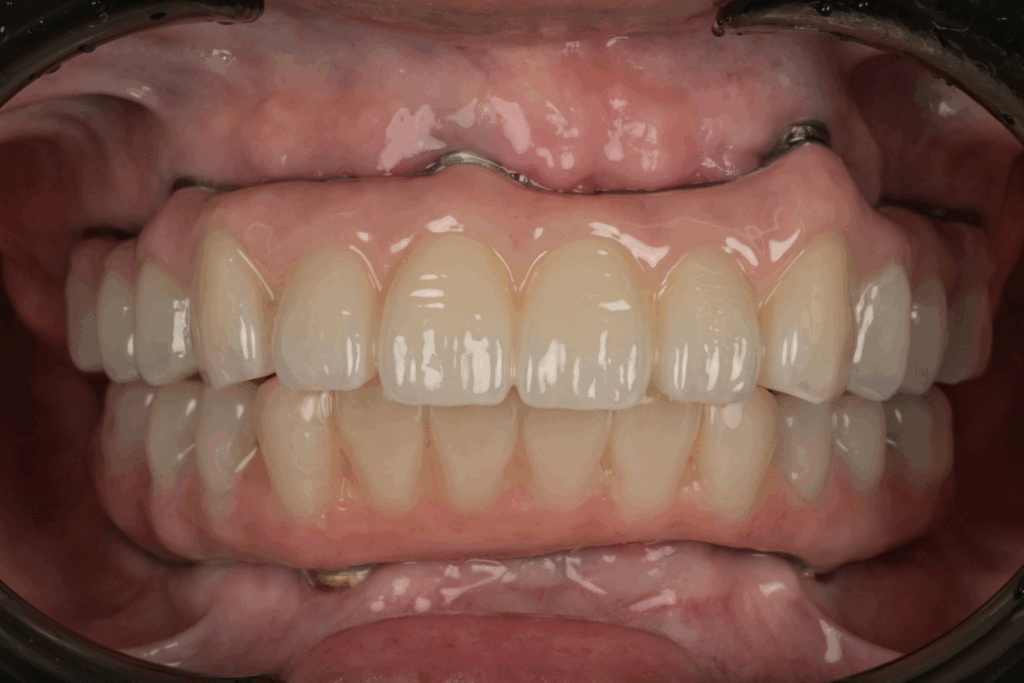

案例2. 上顎+下顎All on X

Before

After